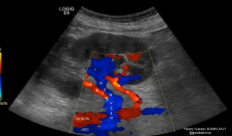

Label the crossed-out structures seen on this image.

IVC

RRA

Aorta

LRA

LRV